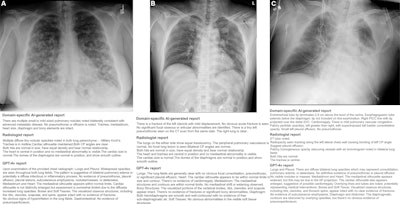

Examples of frontal chest x-rays and associated reports generated by a domain-specific AI model, radiologist, and GPT-4Vision (GPT-4v, OpenAI). (A) The report generated by the domain-specific AI model proposes a diagnosis of advanced metastatic disease, the radiologist report suggests miliary Koch tuberculosis, and the GPT-4Vision report proposes potential pulmonary edema or infection as diagnoses. All three of the radiologists involved in establishing the reference standard for this radiograph reported pulmonary metastasis as the most likely diagnosis. (B) The report generated by the domain-specific AI model accurately detects a left clavicle fracture (arrow) but also erroneously suggests a left pneumothorax. The radiologist and GPT-4Vision reports do not mention these findings, instead describing the lung fields as clear with a normal cardiac silhouette and mediastinum. Of the three radiologists involved in establishing the reference standard for this radiograph, two confirmed the clavicle fracture, while none reported a pneumothorax. The model-generated report also mentions a CT scan, which represents a hallucination, since CT images were not provided as input. (C) The report generated by the domain-specific AI model identifies the presence and location of an endotracheal tube, esophagogastric tube, and right peripherally inserted central catheter. The report also notes mild pulmonary vascular congestion and a left basilar consolidative opacity, while the radiologist report notes pleural effusion and consolidation. The GPT-4Vision report describes diffuse lung opacities and possible cardiomegaly, with no evidence of pneumothorax.Examples of frontal chest x-rays and associated reports generated by a domain-specific AI model, radiologist, and GPT-4Vision (GPT-4v, OpenAI). (A) The report generated by the domain-specific AI model proposes a diagnosis of advanced metastatic disease, the radiologist report suggests miliary Koch tuberculosis, and the GPT-4Vision report proposes potential pulmonary edema or infection as diagnoses. All three of the radiologists involved in establishing the reference standard for this radiograph reported pulmonary metastasis as the most likely diagnosis. (B) The report generated by the domain-specific AI model accurately detects a left clavicle fracture (arrow) but also erroneously suggests a left pneumothorax. The radiologist and GPT-4Vision reports do not mention these findings, instead describing the lung fields as clear with a normal cardiac silhouette and mediastinum. Of the three radiologists involved in establishing the reference standard for this radiograph, two confirmed the clavicle fracture, while none reported a pneumothorax. The model-generated report also mentions a CT scan, which represents a hallucination, since CT images were not provided as input. (C) The report generated by the domain-specific AI model identifies the presence and location of an endotracheal tube, esophagogastric tube, and right peripherally inserted central catheter. The report also notes mild pulmonary vascular congestion and a left basilar consolidative opacity, while the radiologist report notes pleural effusion and consolidation. The GPT-4Vision report describes diffuse lung opacities and possible cardiomegaly, with no evidence of pneumothorax.RSNA